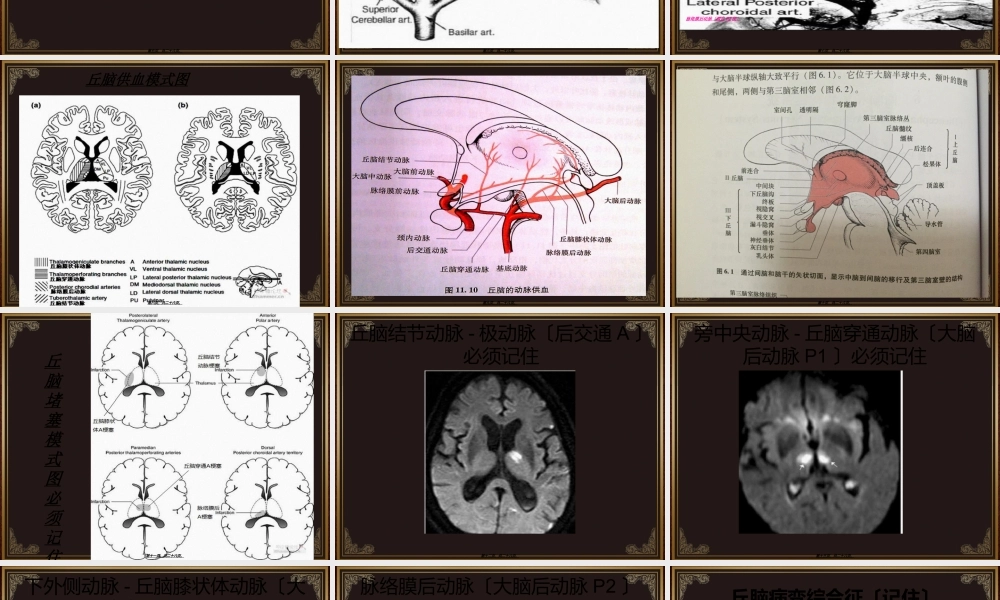

一张表、六个图帮你一劳永逸搞定丘脑血供第一页,共二十六页。基底节区域的解剖关系----尾状核、背侧丘脑、豆状核、内囊〔五局部前、膝部、后肢、豆状核下肢、豆状核后肢〕记忆内囊五局部的投射纤维第二页,共二十六页。丘脑血供的4条血管〔必须记忆〕丘脑综合征第三页,共二十六页。第四页,共二十六页。丘脑的血供〔不用记此张〕•丘脑血供来源较多,以椎-基底动脉系统为主、颈内动脉系为辅。其大的核团供血情况大致为:•丘脑外侧核:后半主要由大脑中动脉的丘脑膝状体动脉供给,前半〔腹前核和腹外侧核等〕由大脑后动脉的结节丘脑动脉供给。•丘脑内侧核:后半主要由脉络膜后内侧动脉的丘脑支供给,前半由大脑后动脉的丘脑穿动脉和后交通动脉的结节丘脑动脉供给。•板内核:主要由丘脑穿动脉供给。•丘脑枕:主要由大脑后动脉的丘脑膝状体动脉和脉络膜后外侧动脉供给。•外侧膝状体:由脉络膜后外侧动脉、丘脑膝状体动脉分支供给。•内侧膝状体:由脉络膜后内侧动脉和丘脑膝状体动脉分支供给。•松果体:由松果体动脉供给。第五页,共二十六页。丘脑血供的4条血管走形图〔必须记忆〕第六页,共二十六页。丘脑血供的4条血管供血区域图〔必须记忆〕下外侧动脉〔源自P2段,别名丘脑膝状体动脉〕导致丘脑综合征丘脑结节动脉〔源自后交通,别名极动脉,丘脑前穿通动脉〕导致丘脑内侧综合征旁中央动脉〔源自大脑后动脉P1段,别名丘脑穿通动脉,丘脑后穿通动脉〕导致红核丘脑综合征脉络膜后动脉〔源自P2段〕第七页,共二十六页。丘脑供血模式图第八页,共二十六页。第九页,共二十六页。第十页,共二十六页。丘脑堵塞模式图必须记住第十一页,共二十六页。丘脑结节动脉-极动脉〔后交通A〕必须记住第十二页,共二十六页。旁中央动脉-丘脑穿通动脉〔大脑后动脉P1〕必须记住第十三页,共二十六页。下外侧动脉-丘脑膝状体动脉〔大脑后动脉P2〕必须记住第十四页,共二十六页。脉络膜后动脉〔大脑后动脉P2〕必须记住第十五页,共二十六页。丘脑病变综合征〔记住〕•丘脑综合征:丘脑膝状体动脉闭塞致丘脑外侧核受损。丘脑外侧核是各种感觉总汇,主要表现为一过性对侧轻偏瘫,持续性的对侧偏侧麻木〔累及触觉和深感觉,较少累计痛觉和温度觉〕,有自发性疼痛,轻度偏身共济失调和实体觉缺失以及舞蹈性手足徐动性静坐不能。•丘脑内侧综合征:丘脑结节动脉〔前穿通A〕闭塞致丘脑内侧核群受损。表现:静止性震颤或者意向性震颤,及舞蹈性手足徐动性静坐不能和丘...

2、本站所有内容均由合作方或网友上传,本站不对文档的完整性、权威性及其观点立场正确性做任何保证或承诺!文档内容仅供研究参考,付费前请自行鉴别。